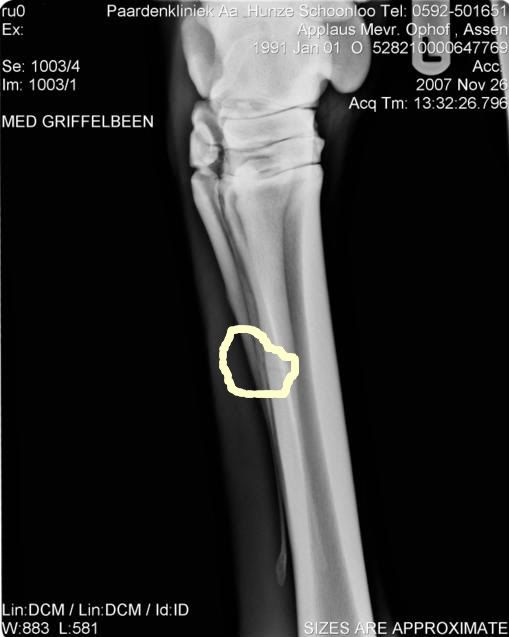

mijn pony had in november een dik been, foto's laten maken en bleek een scheur in het griffelbeen te zijn.

hij heeft enige tijd metacam gehad, moest 10 weken in een paddock en nu rijd ik weer buitenritten van 2 uur, ik spring etc..

wel zit er nog een verdikking-scheiffel dus,maar alles gaat heel erg goed.

heb wel een foto van het breukje:

foto's laten maken is idd een heel goed idee,alhoewel sommige breukjes niet meteen te zien zijn op foto's